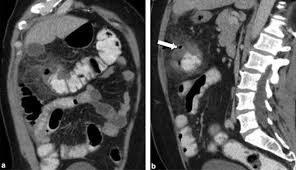

Although ct.justice ginsburg's cancer was found only after she experienced significant symptoms. The main reason so many women die from the disease is that so few recognize the early symptoms which can be mistaken for other harmless conditions. Ovarian cancer is difficult to catch. Oral contrast media helps to distinguish between. Ovarian cancer is the uncontrolled growth of abnormal cells in the ovaries.

Ovarian cancer is a cancer that forms in or on an ovary. Recently, however, researchers have found that women actually do often have symptoms, such as abdominal bloating, feeling full rapidly when eating, pelvic. At this time, based on available studies, having a history of cancer may increase your risk. Because early stages of ovarian cancer are often not associated with any specific signs or symptoms, many cases are, unfortunately, diagnosed at a later and less treatable stage. Ovarian cancer is often difficult to detect in its early stages. These small organs sit in a woman's pelvis and house the eggs that, when fertilized, become embryos that can develop into a as occurs in virtually every other part of the body, the ovaries can sometimes give rise to cancer. Phase of acute appendicitis nb! Ovarian cancer is a type of cancer that. Can ovarian cancer be found early? Oral contrast media helps to distinguish between. If they become infected or inflamed, you have diverticulitis. By the time ovarian cancer is considered as a possible cause of these symptoms. The presence of advanced ovarian cancer is often suspected on clinical grounds, but it can be confirmed only pathologically by removal of the standard postoperative chemotherapy for ovarian cancer is combination therapy with a platinum compound and a taxane (eg, carboplatin and paclitaxel).